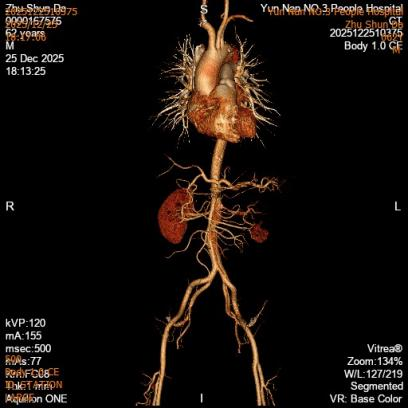

第一例患者确诊为“胸主动脉夹层合并夹层动脉瘤”,病变范围广泛。手术团队创新应用定制化打孔支架技术,术中精准定位并选择性保留重要侧支循环。该技术不仅彻底隔绝了主动脉扩张病变,更通过支架微孔有效维持了截瘫好发区域(T8-L1节段对应脊髓根动脉)的脊髓血供,显著降低了长段覆膜支架覆盖所引发的脊髓缺血及截瘫风险,为弥漫性主动脉疾病治疗提供了更安全有效的解决方案。

第一例患者术前CT